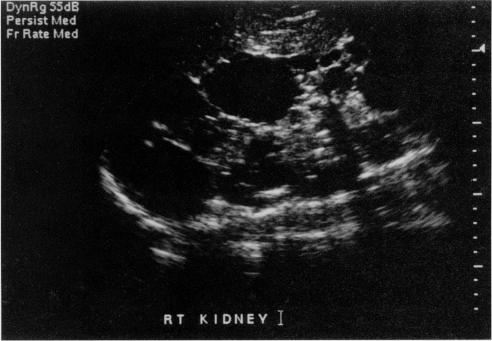

Autosomal dominant polycystic kidney disease is one of the most common hereditary diseases, and frequently has well defined extrarenal manifestations. Very few cases of aortic aneurysms associated with this disorder are described in literature. We report a 42-year-old male with autosomal dominant polycystic kidney disease presenting with dissecting aneurysm of the thoracic aorta.

常染色体显性多囊肾病是最常见的遗传性疾病之一,且常伴有明确的肾外表现。文献中很少描述与该疾病相关的主动脉瘤病例。我们报告了一名42岁患有常染色体显性多囊肾病的男性,其出现了胸主动脉夹层动脉瘤。